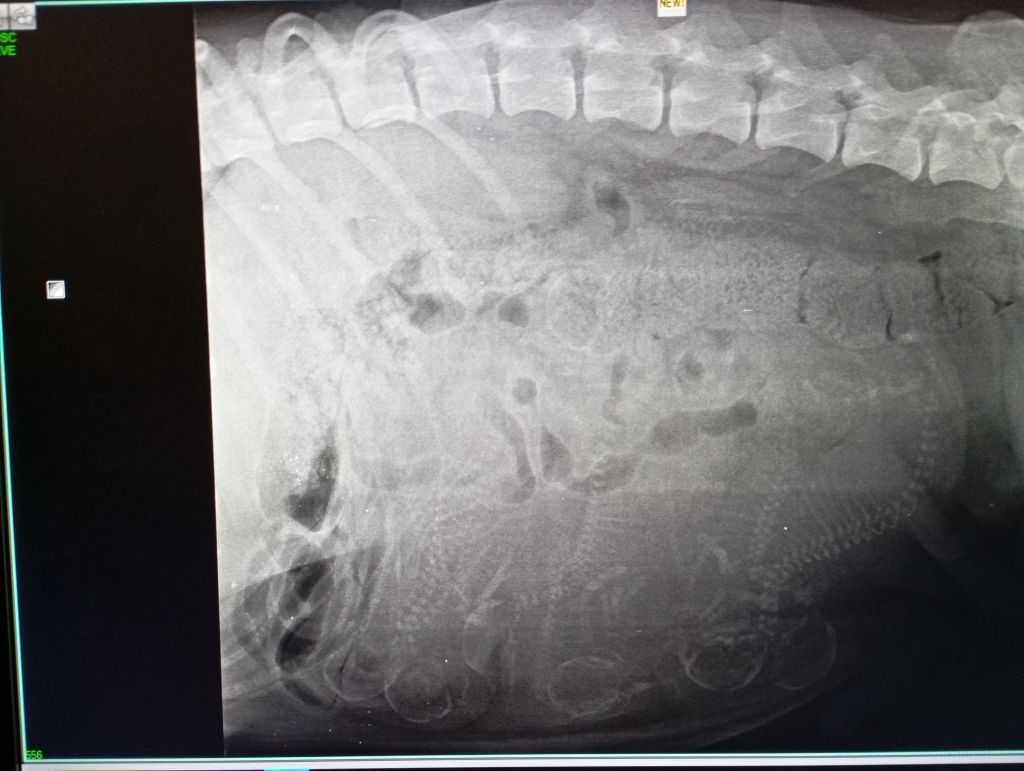

7 bébés attendus dans quelques jours !

Notre Rêve attend 7 bébés

Naissances prévues aux alentours du 10 novembre 2024